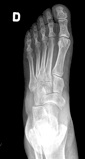

POSICION 4 : PIE LATERAL EN CARGA

Paciente en BIPEDESTACION O CARGA lateral, apoyando la cara lateral del pie sobre el cassete. El haz de rayos es dirigido verticalmente al centro del tarso.El casette en nuestro caso se coloca en el bucky y el paciente en un escalon.

CONSIDERACIONES MEDICAS Posicion 4 : PIE LATERAL EN CARGA

Lateral de pie en bipedaestacion

Posicion de gran uso en ortopedia y complementaria al perfil en decubito, es importante especificar si el apoyo es monopodalico, en patologia de sobreesfuerzo, puede ser de importancia el observar los puntos de contacto, en la medida en que los arcos plantares son respetados podremos descartar patologia mas que observarla, y no olvidar que es un enfoque complementario, algunos prefieren este enfoque para observar la medio tarsiana y su estado articular ,a veces tambien es necesario acompañar de un frente en apoyo para complementar la observacion. Dr.Aramayo